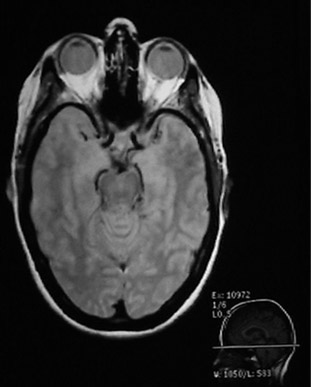

Since the MRI uses proton NMR, it images the concentration of protons. Many of those protons are the protons in water, so MRI is particularly well suited for the imaging of soft tissue, like the brain, eyes, and other soft tissue structures in the head as shown at left. The bone of the skull doesn't have many protons, so it shows up dark. Also the sinus cavities image as a dark region.